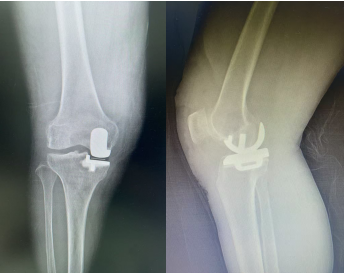

术后影像资料

手术很顺利,术后在医护团队的精心照护下,张奶奶的恢复比预期还要快。出院那天,她已经能稳稳当当地自己走路,困扰了20多年的膝盖痛基本消失了,脸上也露出了久违的笑容。